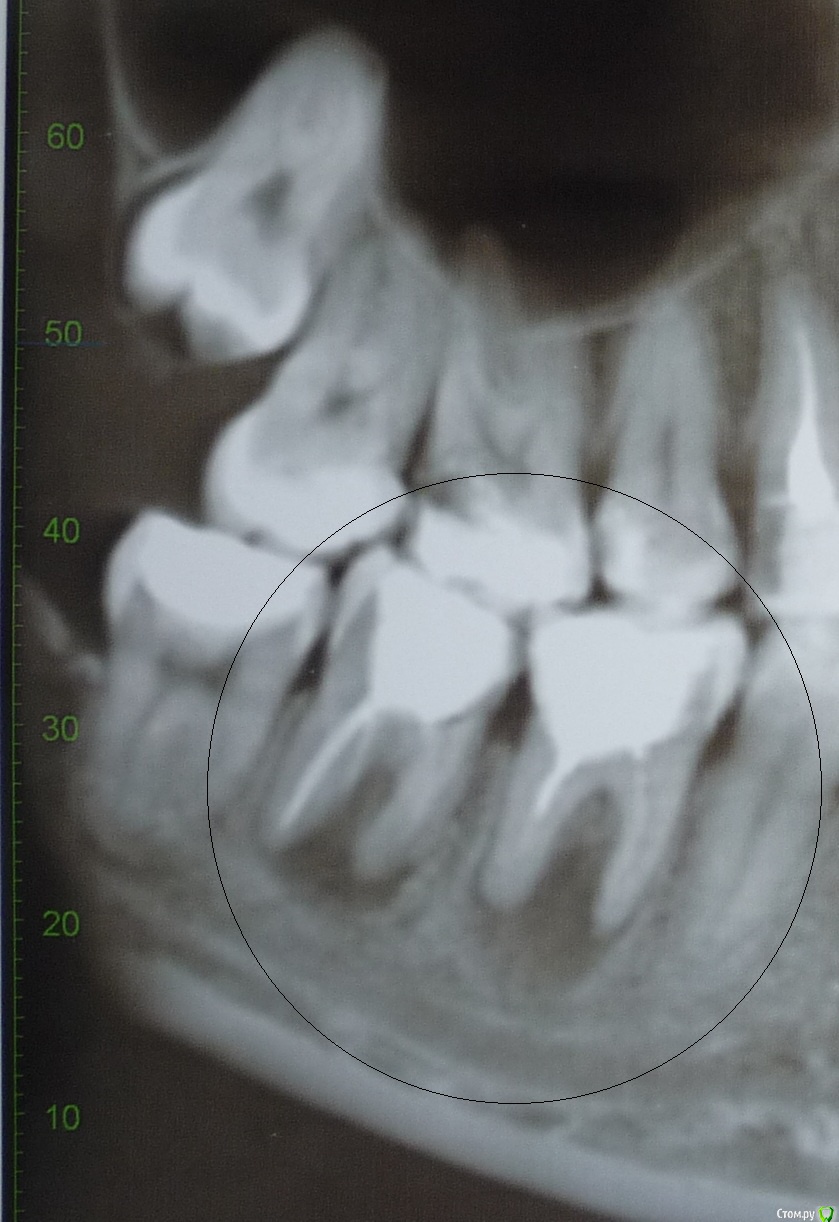

12345k Опубликовано 23 августа, 2019 Поделиться Опубликовано 23 августа, 2019 Здравствуйте!Подскажите, пожалуйста, как лучше поступить с зубами 25, 46, 47? Воспаление обнаружилось год назад на рентгеновском снимке. У зубов имеются свищи. Спасибо. Ссылка на комментарий

St. Опубликовано 2 сентября, 2019 Поделиться Опубликовано 2 сентября, 2019 Добрый день.Если еще актуально. Корневые каналы можно перелечить. Шансы на успех достаточно высокие .Могут возникнуть вопросы с 47 по этому снимку не понятно, но там может быть перфорация или трещина. Ссылка на комментарий

12345k Опубликовано 31 января, 2020 Автор Поделиться Опубликовано 31 января, 2020 В продолжение моей темы. Мне перелечили зуб 25: распломбировали, промыли каналы, закладывали кальсепт с йодоформом на 2 недели, затем запломбировали каналы на постоянной основе. В процессе несколько раз делали снимки (они не на руках). Снимок до лечения выложен ранее.Хотела бы задать вопрос уважаемым докторам форума. Может, кто-нибудь ответит? К своему доктору пока нет возможности попасть.До перелечивания на десне рядом с зубом 25 был свищ, из которого самостоятельно отделялось содержимое. После промывания каналов и кальция прекратились выделения из свища, но на десне был виден небольшой круглый шрам. Спустя месяц после пломбировки каналов снова начались периодические скудные выделения из свища белого цвета.Означает ли это, что инфекция не устранена или находилась не в каналах зуба? Насколько неблагоприятен прогноз? Насчет резекции доктор сразу сказал, что этот способ на подойдет.Спасибо всем, кто откликнется. Ссылка на комментарий

red_butler Опубликовано 31 января, 2020 Поделиться Опубликовано 31 января, 2020 Означает ли это, что инфекция не устранена или находилась не в каналах зуба? да Насколько неблагоприятен прогноз? покажите снимки Ссылка на комментарий